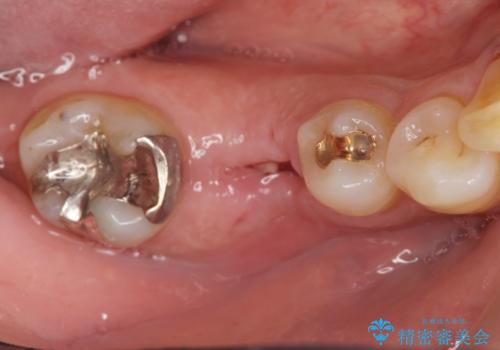

- 銀歯がダツリし、支える歯が破れている状態で抜歯を余儀なくされました。

短期間での咬合昨日の回復、手術を希望されなかったのでブリッジによる咬合機能回復を計画します。

- 24万円(仮歯・フルジルコニアクラウン×3)費用は治療当時の料金となります